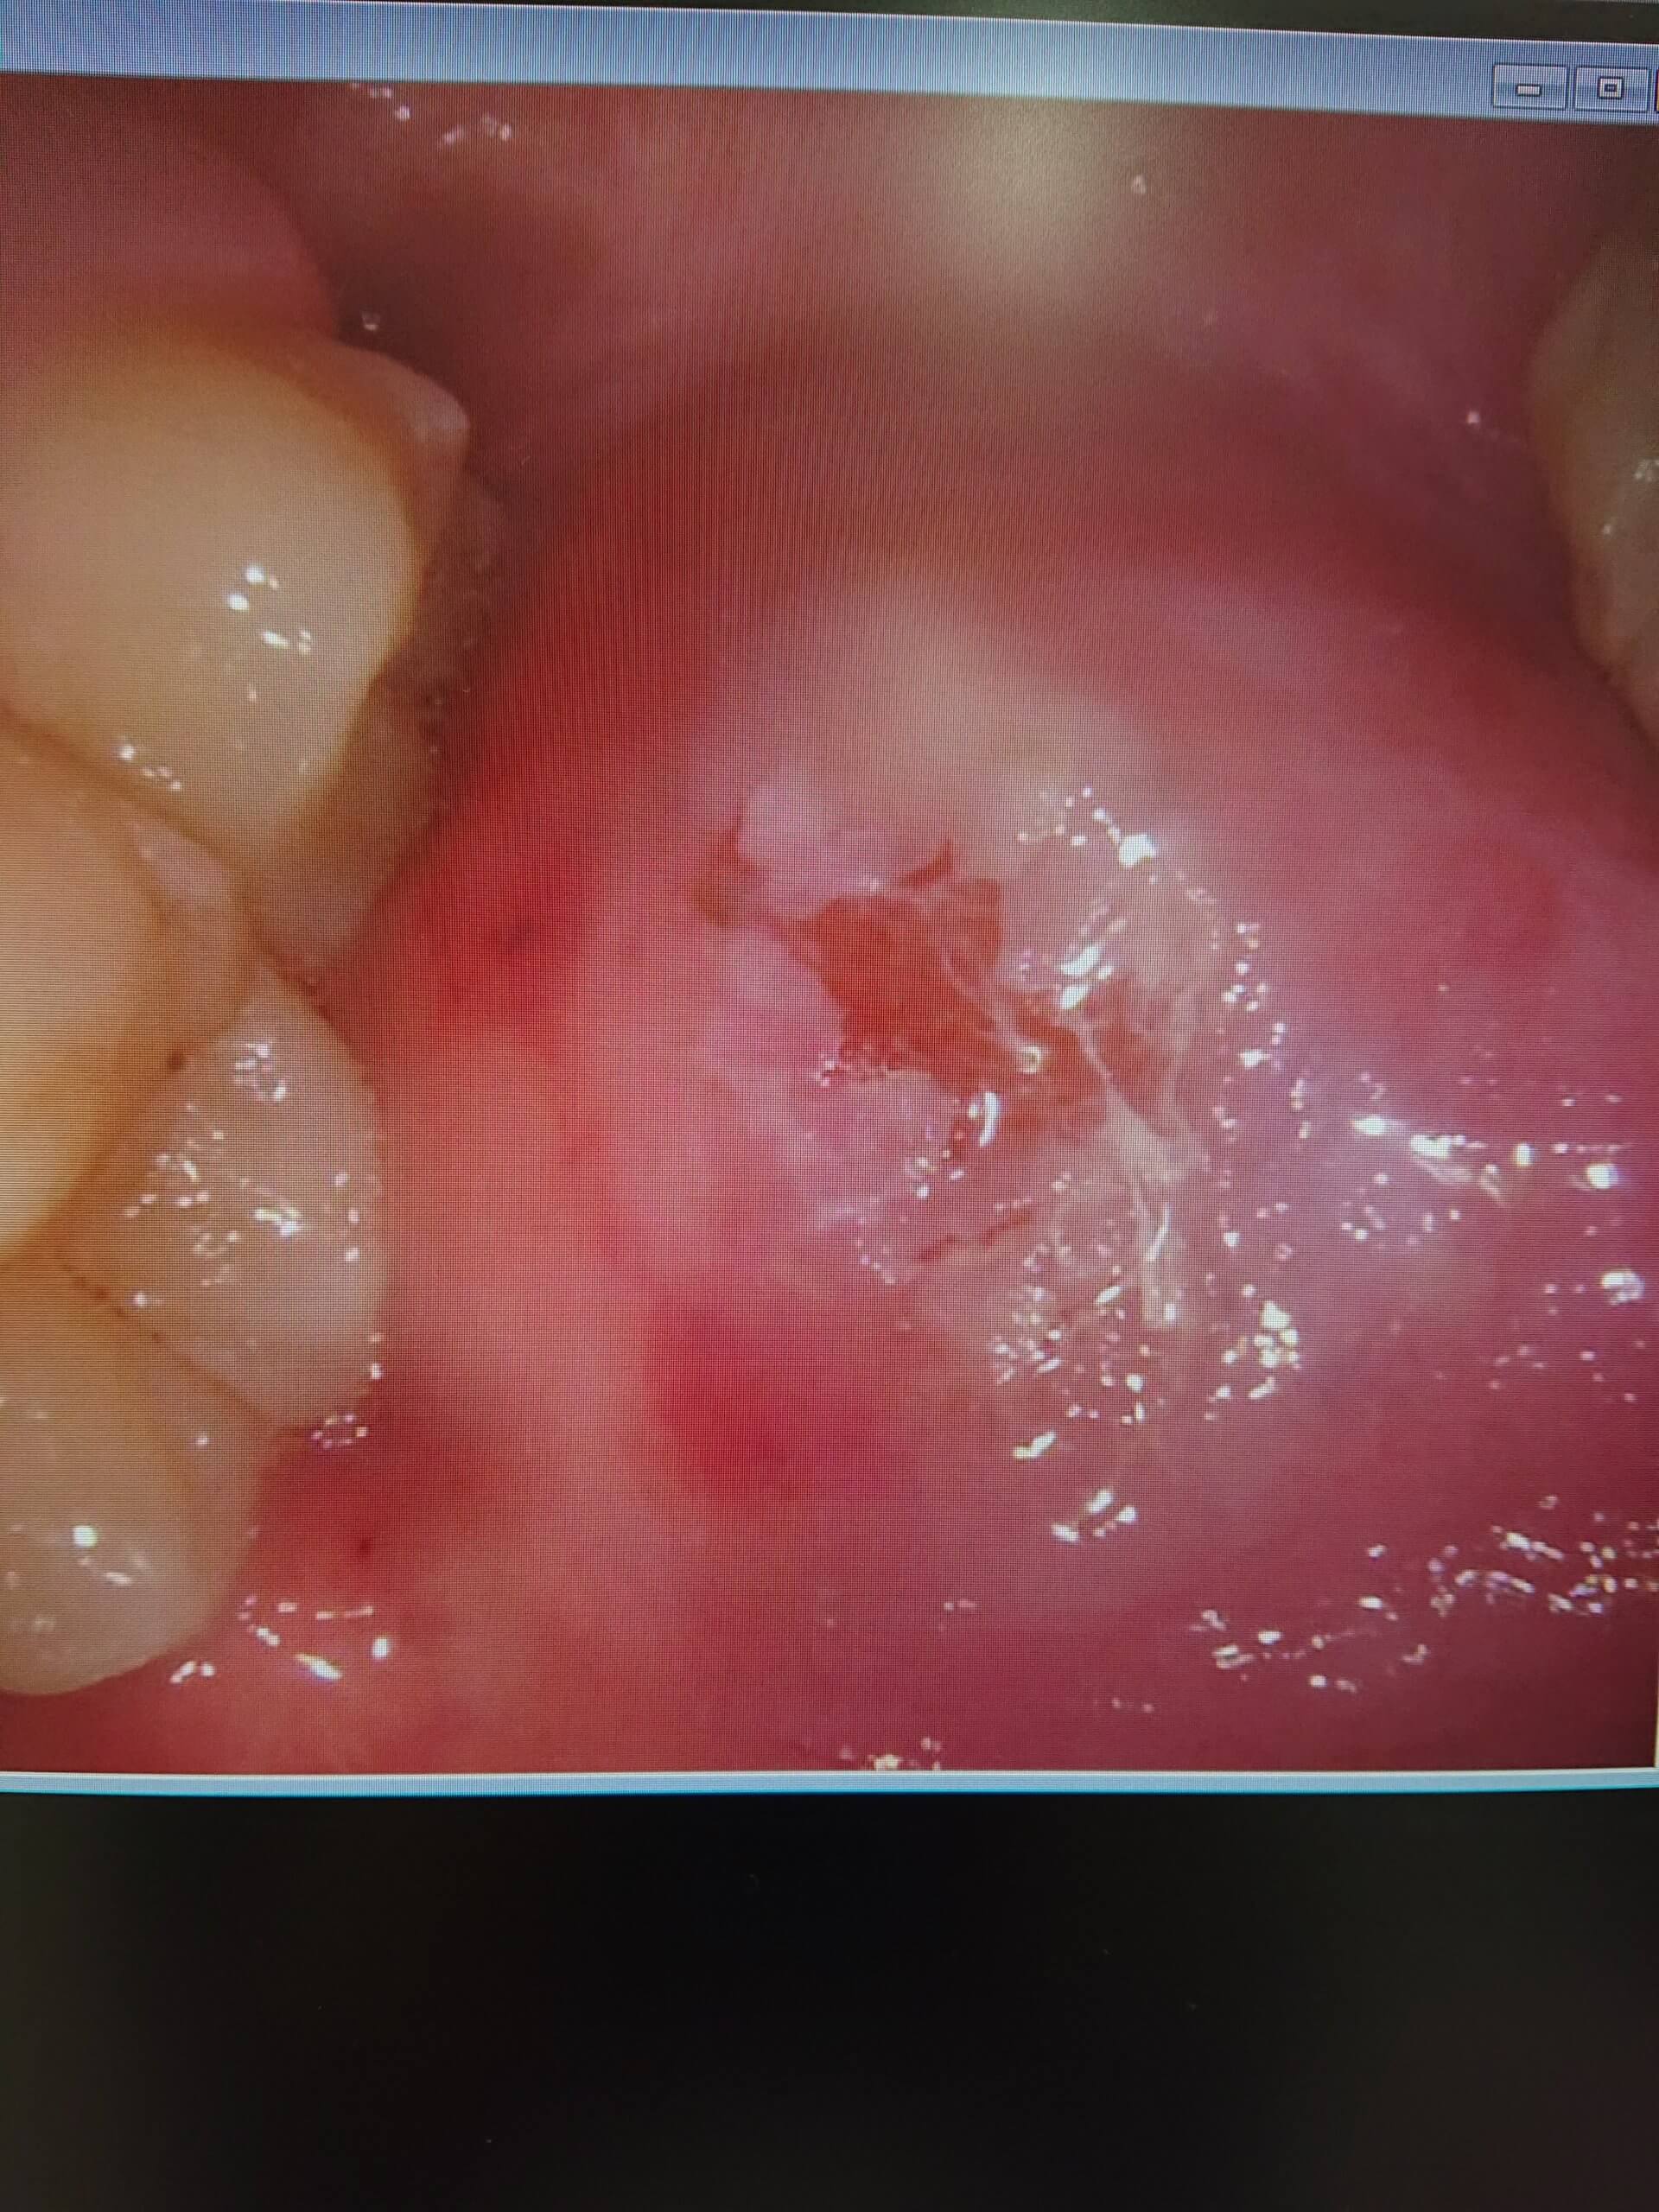

口内炎噛んじゃった💦

口内炎を思いっきり噛んでしまったそうです

噛んだ時には血の味がしただけで痛みはなかったそうです

しかし、傷が大きくすぐに治るとは思わなかったので院長に診察してもらい口腔内軟膏を患者さんに処方していただきました